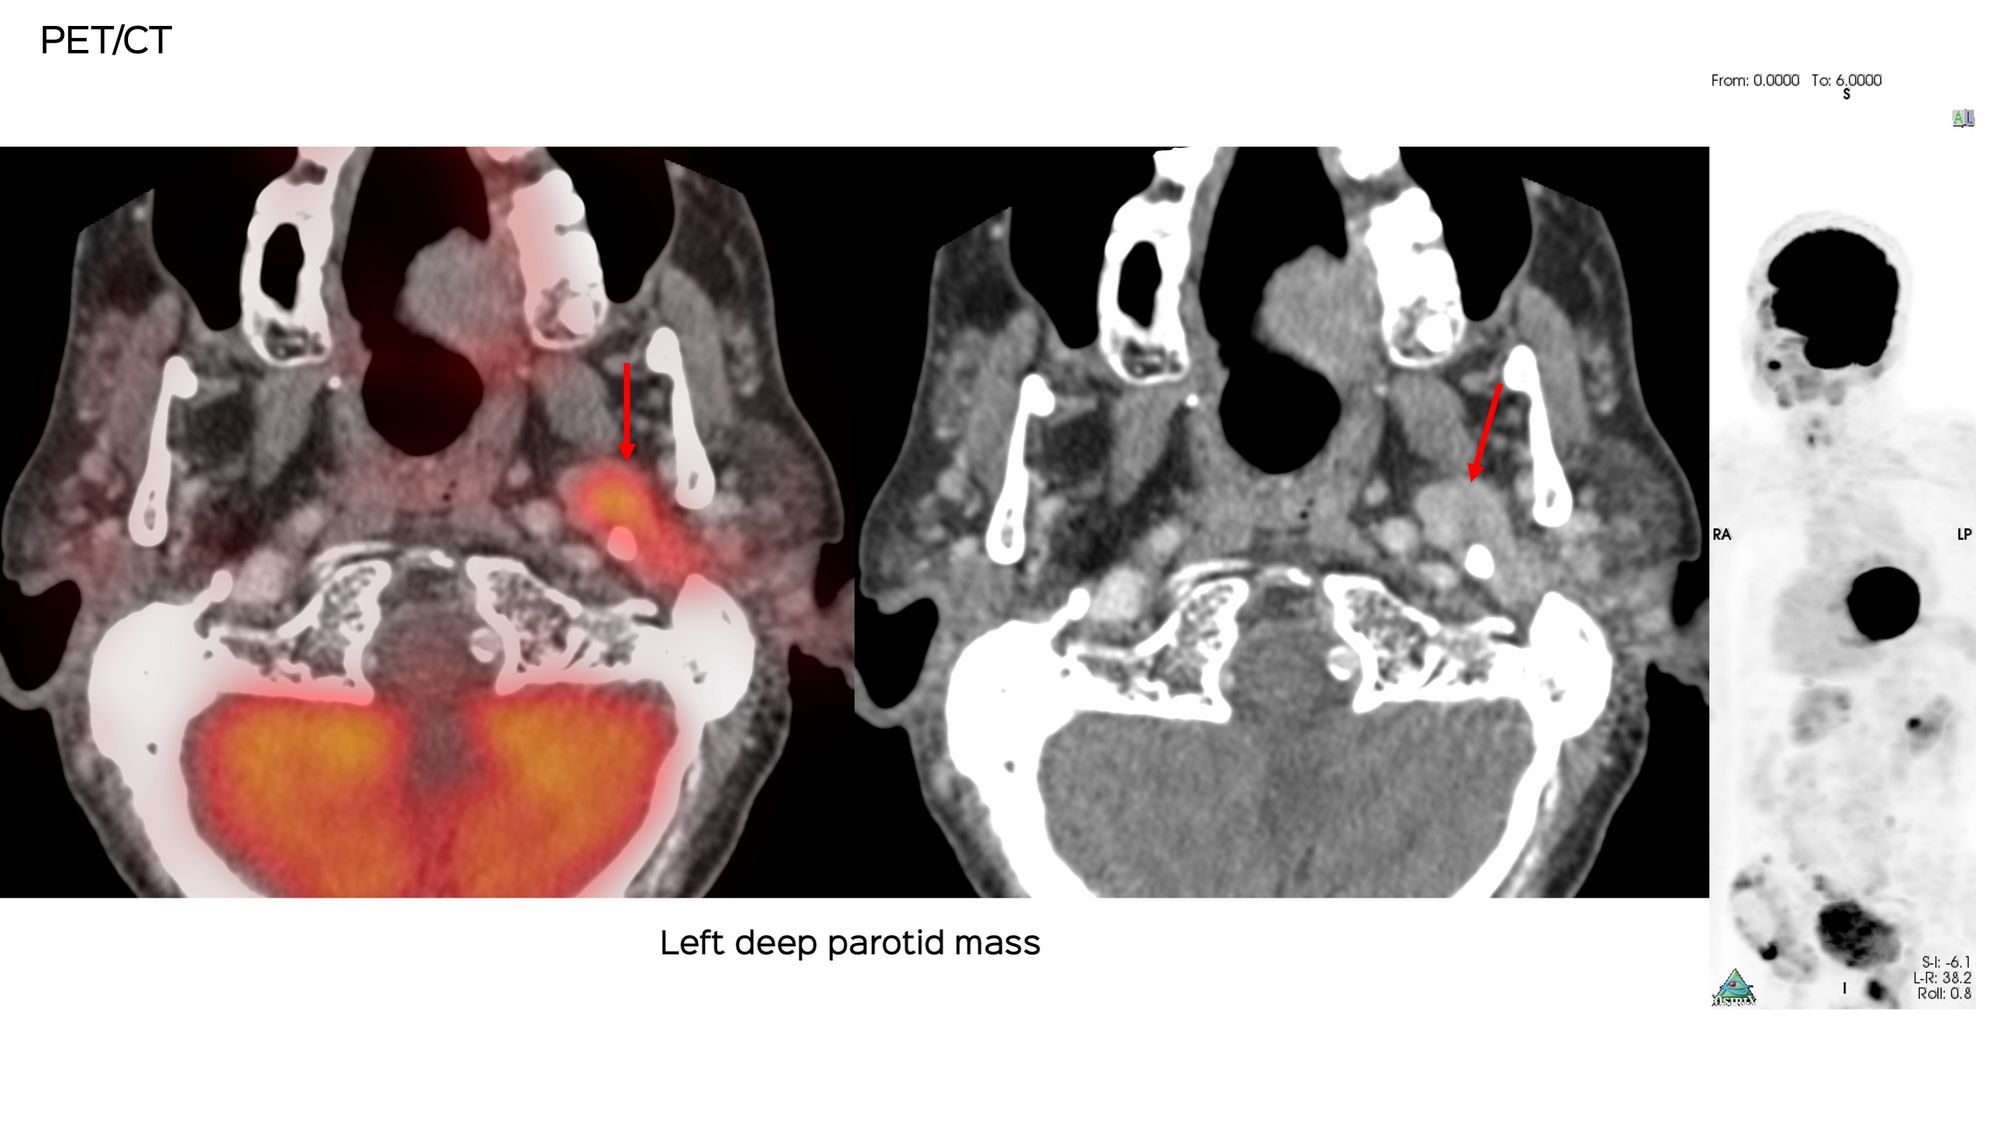

An 81-years old was found to have a left deep parotid mass.

The surgeon asked for a CT guided biopsy. This was the appearance at the time of the biopsy